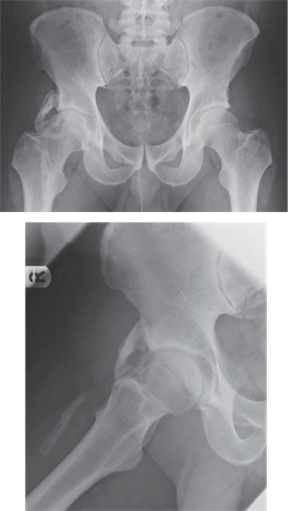

What condition is illustrated here?

Avascular necrosis of the femoral head with segmental collapse.

Can you describe any classifi cation systems for this condition? What stage is shown in the radiographs above?

There are many classifi cation systems described for osteonecrosis of the hip. The Ficat and Arlet (1980) system describes X-ray appearances and is one of the most simple to use:

Stage 1: no bony changes seen on plain X-ray

Stage 2: sclerotic and cystic changes within the femoral head

Stage 3: subchondral collapse and distortion of the femoral head

Stage 4: secondary osteoarthritis with decreased joint space and articular collapse

T he radiographs show Ficat and Arlet stage 4 changes. There is distortion and collapse of the femoral head. The lateral view illustrates the โcrescent signโ associated with subchondral collapse.

How would you manage a patient presenting with this condition. What treatment options are available?

Treatment of early osteonecrosis of the femoral head aims to relieve pain and preserve the congruency of the hip joint. In the later stages of the disease arthroplasty procedures are usually required. Investigations used to help stage the disease include plain radiography, bone scans, and MRI.

Treatment for early stages (pre-collapse) may include: z Observation and analgesia z Treatment of any underlying medical conditions z Protected weight-bearing (little evidence)

z Core decompression ยฑ bone grafting or vascularized grafts Treatment for later stages (post-collapse) may include: z Realignment osteotomy z Arthrodesis z Replacement arthroplasty (conventional total hip arthroplasty or resurfacing)